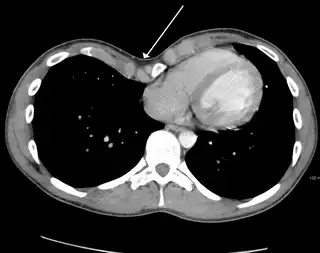

-

Cross sectional scan of a chest with pectus excavatum -

Many scales have been developed to determine the degree of deformity in the chest wall. Most of these are variants on the distance between the sternum and the spine. One such index is the Backer ratio which grades severity of deformity based on the ratio between the diameter of the vertebral body nearest to xiphosternal junction and the distance between the xiphosternal junction and the nearest vertebral body.[19] More recently the Haller index has been used based on CT scan measurements. An index over 3.25 is often defined as severe.[20] The Haller index is the ratio between the horizontal distance of the inside of the ribcage and the shortest distance between the vertebrae and sternum.[21]

Chest x-rays are also useful in the diagnosis. The chest x-ray in pectus excavatum can show an opacity in the right lung area that can be mistaken for an infiltrate (such as that seen with pneumonia).[22] Some studies also suggest that the Haller index can be calculated based on chest x-ray as opposed to CT scanning in individuals who have no limitation in their function.[23]